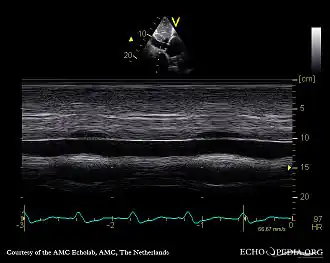

Обязательно проведение инструментальных методов исследования: